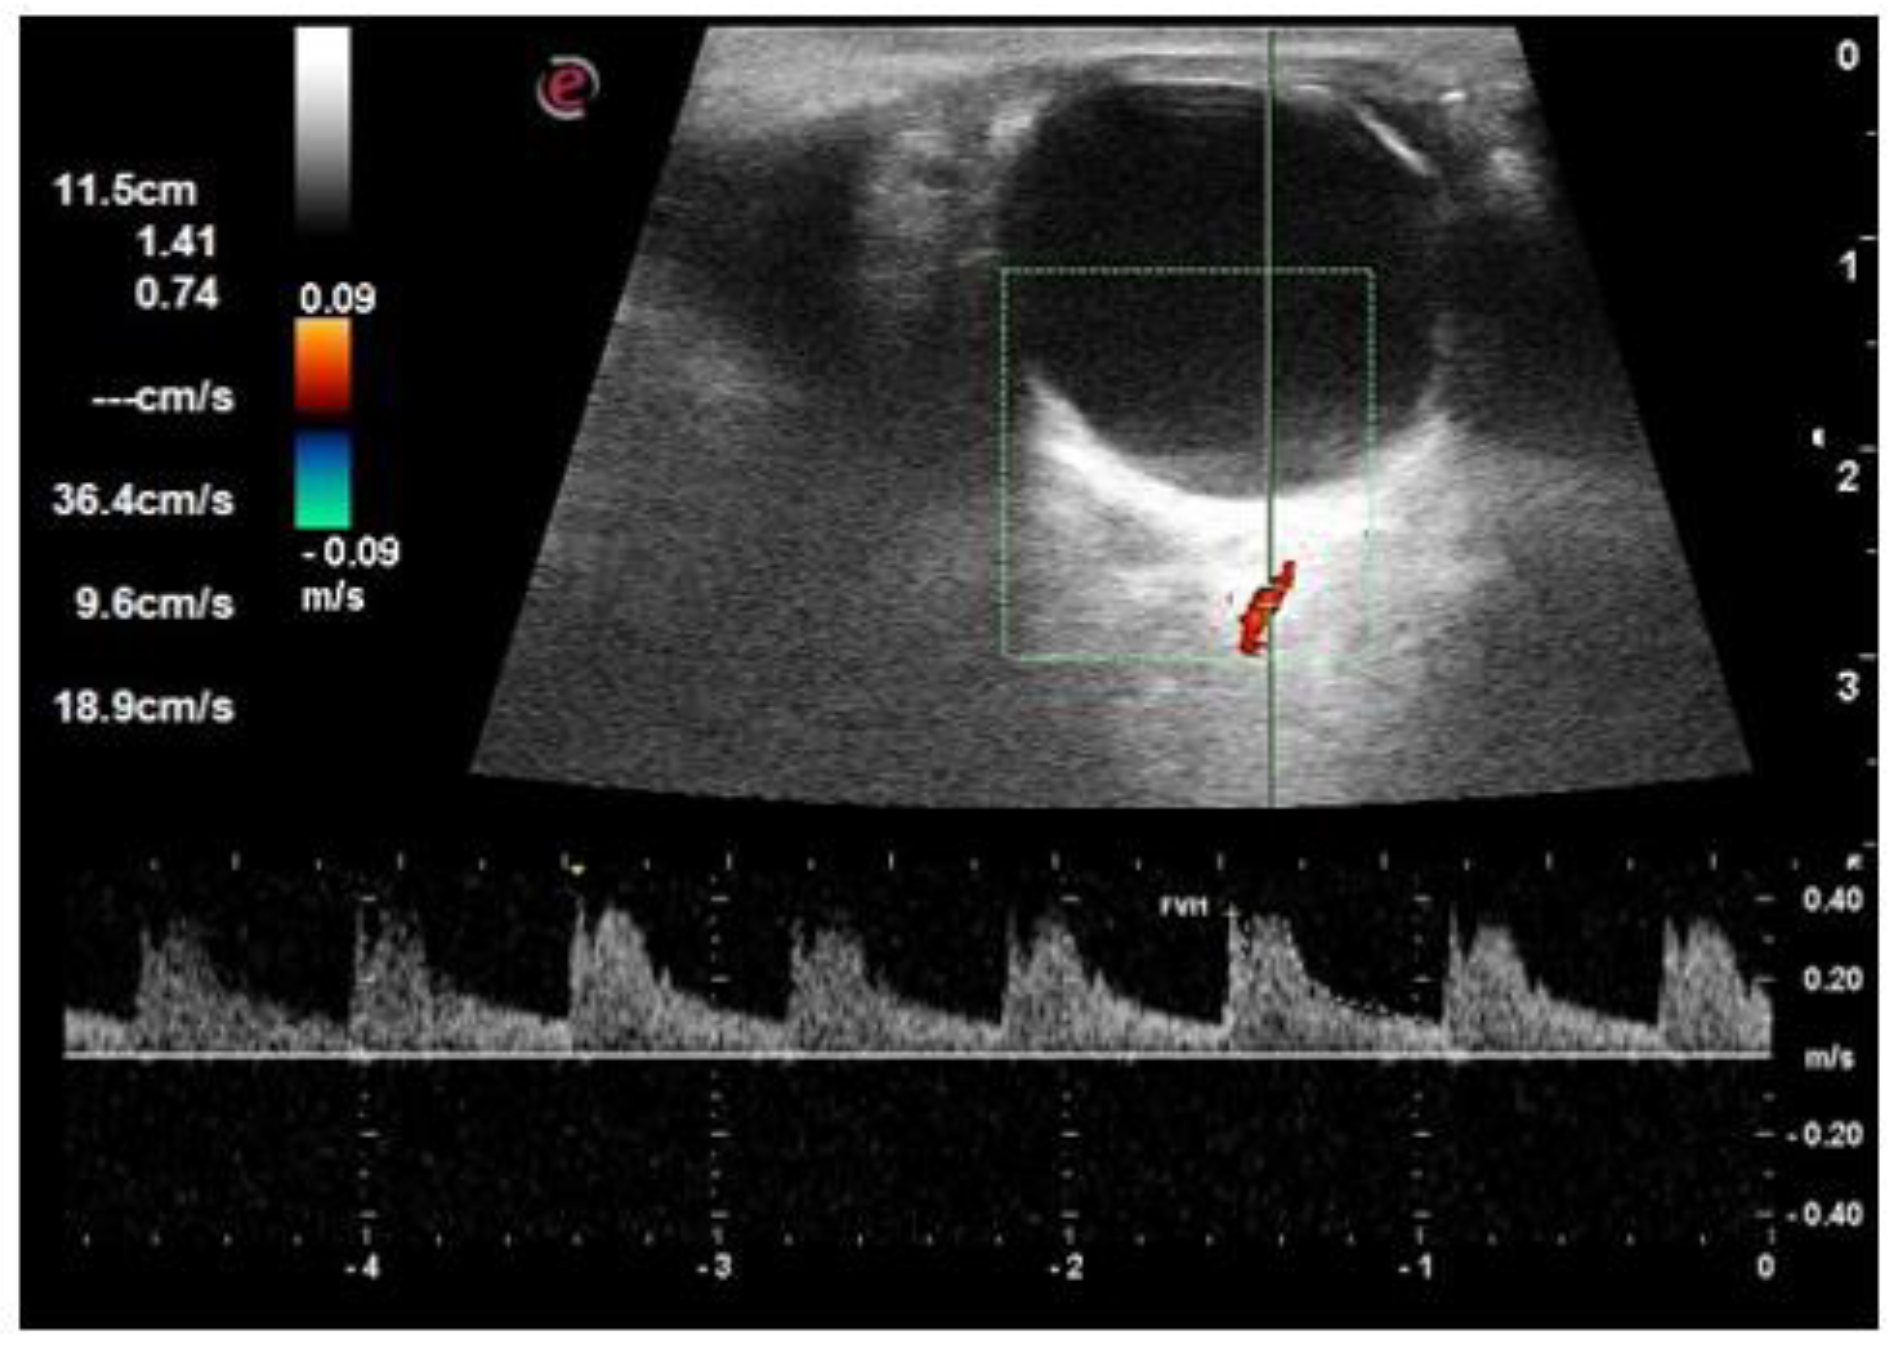

| PSV of ophthalmic artery (cm/s) | 31.9 ± 2.6 | 32.7 ± 3.0 | 33.8 ± 3.8 | 0.550 |

| EDV of ophthalmic artery (cm/s) | 8.7 ± 0.9 | 8.8 ± 1.6 | 8.3 ± 1.3 | 0.240 |

| RI of ophthalmic artery | 0.72 ± 0.02 | 0.73 ± 0.03 | 0.75 ± 0.03 | <0.001 |

| PSV of central retinal artery (cm/s) | 16.1 ± 1.9 | 15.8 ± 3.1 | 14.2 ± 2.7 | 0.010 |

| EDV of central retinal artery (cm/s) | 5.1 ± 0.7 | 4.8 ± 1.1 | 3.9 ± 1.0 | <0.001 |

| RI of central retinal artery | 0.68 ± 0.03 | 0.69 ± 0.03 | 0.72 ± 0.04 | <0.001 |